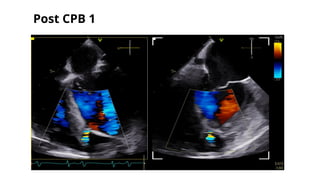

POST CPB 1

o Going on CPB - U/E,

o CPB 1- CABG * 2G, VSR patch

o Coming off CPB1 - NSR with supports Levosimendan@0.075, Adr@0.05 & Vaso @0.0003

o Post CPB 1 TEE- initially showed a color jet within the RV in the transgastric images which were

not traced to LV in the midesophageal images. Continued imaging revealed this colour jet to be

getting prominent.

o PA sO2 - 71%, RA sO2 - 67%

o Went on CPB-2 @ protamine 75%

o For CPB 2- Inj.Heparin 5mg/kg repeated.